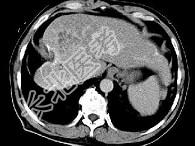

- 单项选择题女性患者,56岁, 腹胀、双下肢浮肿、乏力、食欲不振,影像所见如下图, 最佳的诊断是 ( )

A、肝炎后肝硬化并肝癌

B、局限性脂肪肝

C、原发性肝癌

D、血吸虫肝硬化并肝癌

E、酒精性肝硬化并肝血管瘤